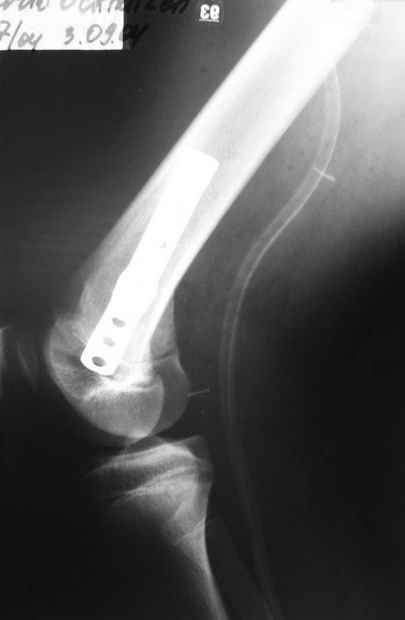

Как вариант решения прогрессирующей вальгусной деформации коленного сустава я бы предложил косую остеотомию дистального отдела бедра с фиксацией пластиной и компрессирующим винтом.

Взгляните на снимки , может быть это вам поможет.

Около 5 лет применяю этот тип дистальной остеотомии бедра для коррекции механической оси Н/К ( более 20 случаев) - достаточно эффективная операция.